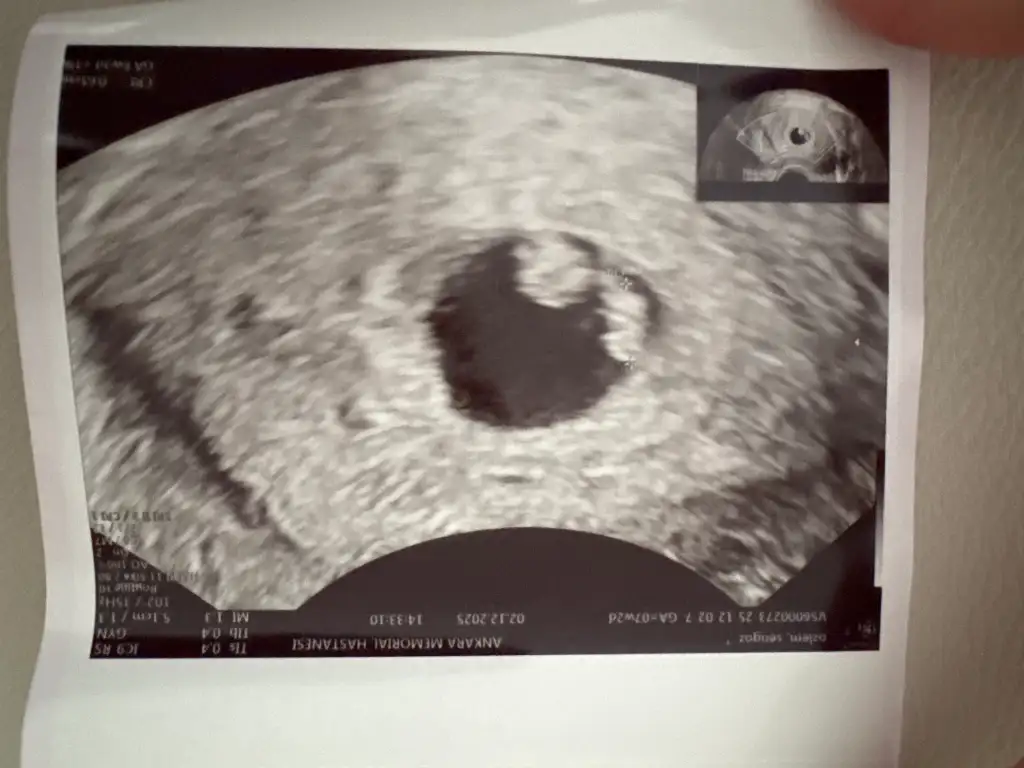

Cinsiyet tahmini

İlk gebeliğim çok merak ediyoruz farklı bi açıdan da fotoğrafı var göndereyim mi bakın bi daha